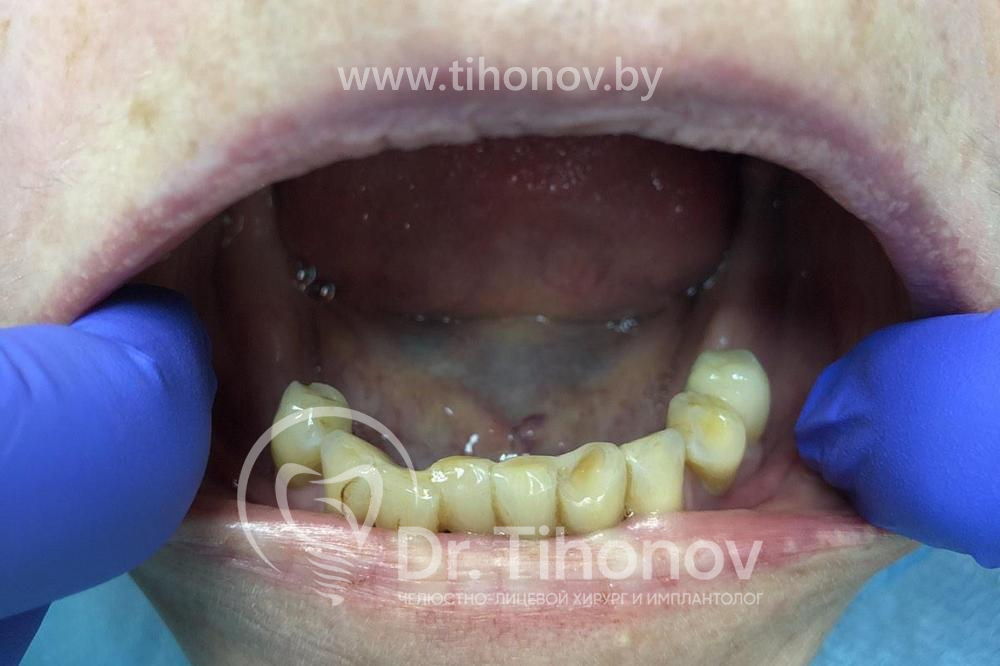

Пациентка обратилась с жалобами на отсутствие жевательных зубов на обеих челюстях и на подвижность оставшихся передних зубов, из-за чего начались проблемы с желудком вследствие невозможности качественно пережевывать пищу.

При изучении данных 3D-исследования, был выявлен недостаток высоты и толщины костной ткани на обеих челюстях. В связи с этим пациентке был предложен вариант быстрого и эффективного восстановления зубов на верхней и на нижней челюстях с использованием методики All-on-6 (все на 6-ти): были удалены оставшиеся зубы, установлены 6 имплантатов на верхней и 6 имплантатов на нижней челюстях, в течение 5 дней изготовлены и зафиксированы в полости рта несъемные эстетичные и функциональные протезы на обе челюсти. Таким образом, пациентка обзавелась красивой улыбкой за 5 дней.